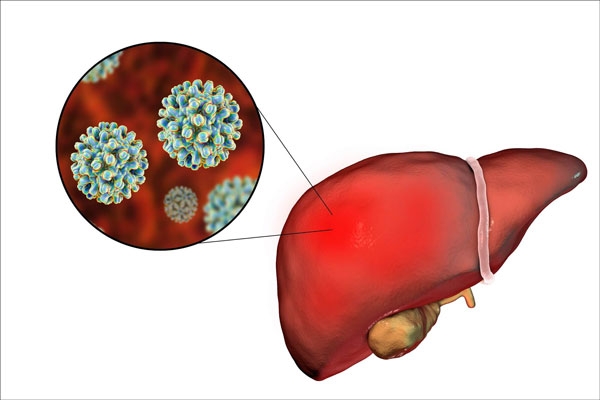

نبذة عن التهاب الكبد a وb وc

يتعرض الكبد كغيره من باقي الأعضاء في جسم الإنسان إلى الالتهابات والأمراض الناتجة عن الجراثيم والفيروسات المولدة لهذه الأمراض، ومن أهمها التهاب الكبد بأنماطه الثلاث a ,b ,c.

يعد التهاب الكبد من النمط c أحد أخطر الأنواع، يأتي بالمرحلة الثانية من الخطورة التهاب الكبد b، ثم التهاب الكبد a، وعادة ما تأتي العدوى الفيروسية نتيجة الشروط غير الصحية التي يتعامل فيها الشخص السليم مع الشخص المصاب، وسنوضح لكم في المقال الفرق بين التهاب الكبد a b c، فتابعوا معنا.